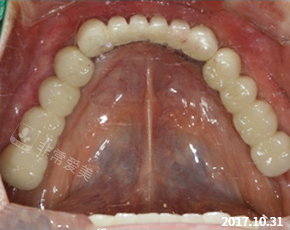

四、治疗后对比:从解剖重建到生命质量提升(图2深度解析)

4.1 解剖与功能改善

咬合效率:术后咀嚼效率改善至正常值95%,可轻松咬碎坚果;

关节健康:颞下颌关节弹响消失,开口度从35mm增至45mm;

骨结合结果:种植体ISQ值(稳定性参数)达78,远超安心阈值65。

4.2 美学结果突破

前牙美学:微笑时前牙显示量增加20%,切端对称性理想,颜色与天然牙融为一体;

软组织改善:牙龈高度改善至邻牙水平,乳头充满度较高,无“黑三角”缺陷。